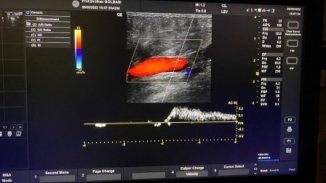

Venöz yetmezlik tanısında en etkili yöntem Doppler ultrasondur. Dopler ultrasonda bacaktaki derin, yüzeyel ve bu ikisini birleştiren perforan venler değrlendirilir. Bu değerlendirmede, bu venlerin çapları, içlerindeki kapakçıklarda geriye doğru kaçak olup olmadığı değerlendirilir.

Video. Varis tedavisinde doppler ultrason ile muayenesi

Bu değerlendirmede hasta yatar pozisyonda ve ayakta çeşitli manevralar yaparak toplardamarların başta derin ve yüzeyel damarın birleştiği kasık bölgesi olmak üzere bütün toplardamarlar değerlendirilir. Buna bağlı olarak kaçağın süresine, damarın çapına bağlı olarak venöz yetmezliğin derecesi değerlendirilir. Normalde toplardamarların 0,5 sn kaçırması normal kabul edilir. Kaçak süresi 1sn hafif, 2 sn orta, 3sn ve üzerinde ise ciddi kaçak olarak kabul edilir. Ayrıca, çaplarında 4-5,5 arasında olması beklenir.

Resim. Ayak bileği ve bacakta ödem, renk değişikliğinde dopplerde ciddi kaçak saptanıyor